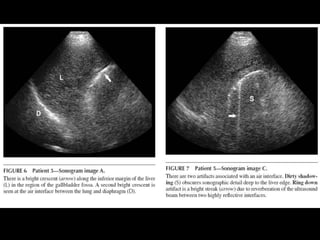

EMPHYSEMATOUS CHOLECYSTITIS

•   Emphysematous cholecystitis < 1%

•   ATC: elderly, male, dbt

•   Mortality rate: 15% (1.4 cholecystitis)

•   TTO: CX because of perforation

•   Test of choice: Abdominal RX

• Air in the biliary system also occurs w/ enteric-

biliary fistula (gallstone ileus or surgical

anastomosis)

– Gallbladder is collpased rather than distended

GAS IN THE GALLBLADDER WALL IS

PATHOGNOMONIC FOR

BEST INITIAL TEST?

• ULTRASONOGRAPHY : bright echogenic

crescent in the gallbladder fossa with dirty

shadowing and ring down artifacts.

– Similar:

• Contracted stone-filled gallbladder (WES)

• Porcelain gallbladder w/ calcified wall due to chronic

cholecystitis

• CONFIRMATION:

– Abdominal rx or CT

Emphysematous cholecystitis < 1% • ATC: elderly, male, dbt • Mortality rate: 15% (1.4 cholecystitis) • TTO: CX because of perforation • Test of choice: Abdominal RX

• Air inthe biliary system also occurs w/ enteric- biliary fistula (gallstone ileus or surgical anastomosis) – Gallbladder is collpased rather than distended

GAS IN THEGALLBLADDER WALL IS PATHOGNOMONIC FOR EMPHYSEMATOUS CHOLECYSTITIS

BEST INITIAL TEST? •ULTRASONOGRAPHY : bright echogenic crescent in the gallbladder fossa with dirty shadowing and ring down artifacts. – Similar: • Contracted stone-filled gallbladder (WES) • Porcelain gallbladder w/ calcified wall due to chronic cholecystitis • CONFIRMATION: – Abdominal rx or CT